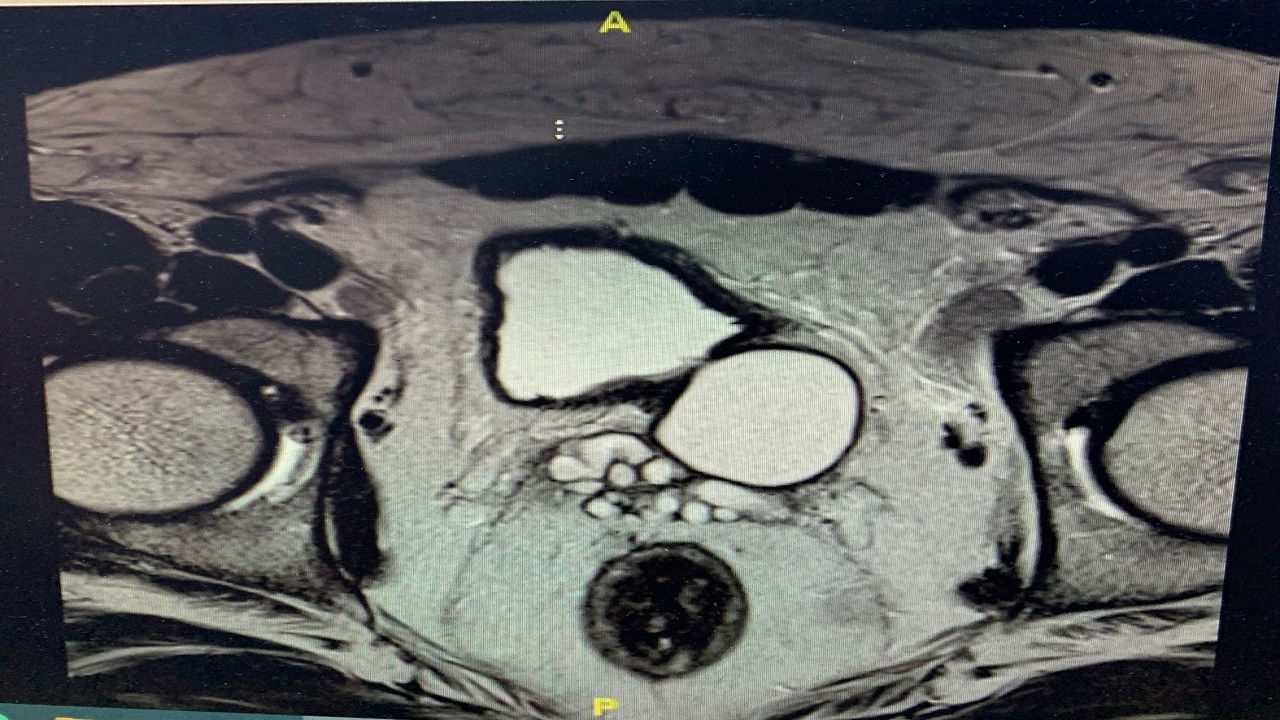

تسجيل اول حالة “لمتلازمة زينر الثلاثية” في مكة